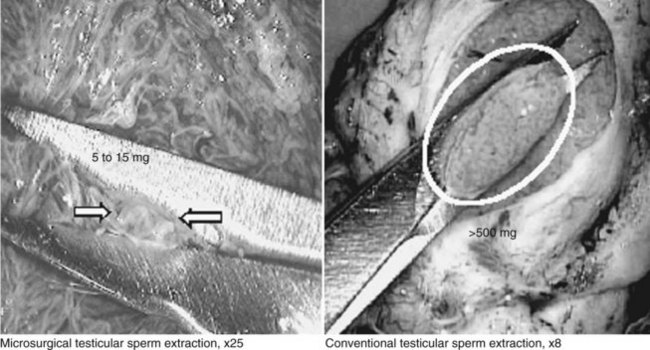

For men with unreconstructable obstruction, as well as men with nonobstructive azoospermia, surgical retrieval of sperm to achieve fertilization, pregnancy, and live birth with IVF and ICSI is a feasible management option. The development and recent refinement of the various techniques of surgical sperm retrieval, from testes, epididymides, or seminal vesicles with percutaneous or open surgical approaches, have expanded the armamentarium of urologists treating infertile men. In particular, the employment of the operating microscope to evaluate and identify individual seminiferous tubules more likely to contain sperm has significantly improved the success of testicular sperm extraction (Schlegel, 1999) while minimizing morbidity significantly (Tsujimura et al, 2002; Ramasamy et al, 2005).